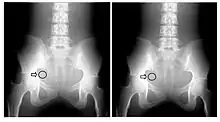

File 6.21: An interpretation of a Receiver Operating Characteristic (ROC) curve as the degree of separation between two Gaussian distributions, where the perpendicular line marks the decision point. Positive diagnoses lie to the right of this line, while negative diagnoses lie to the left. The decision point defines a point on the ROC curve. See text for further details.

Image quality can also be assessed using descriptive statistics, e.g. accuracy, sensitivity and specificity, with large patient cohorts and validated diagnoses. Here, a truth table is constructed which details the number of true and false, positive and negative radiology interpretations - see Figure 6.21. Note that this perspective is similar to that adopted in the famous Known Knowns remark used in US politics!

Receiver Operating Characteristic (ROC) curves can be derived from such cohort data. This method is based on signal detection theory, where human observers score their level of confidence for their interpretations of the image data. ROC curves are obtained by plotting the probability of true positive results against that of false positives. A diagonal line is obtained in the case of random decisions and actual curves lie above this line. Decision levels towards the extreme top right of the curve is referred to as Over-Reading while those close to the origin are referred to as Under-Reading. A major advantage of such data analysis is that it yields a single number - the area under the ROC curve - which describes the overall performance of a diagnostic system. It should be appreciated, however, that ROC analysis requires the availability of a superior standard of truth, e.g. biopsy results, an adequate number of diseased and control subjects as well as a number of qualified observers.